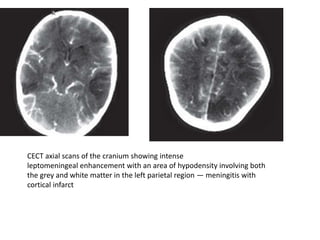

Central Nervous System Infarction

• Central nervous system infarction associated

with meningitis occurs because of

inflammation-induced arterial spasm or

because of direct inflammation of the walls of

arteries and arterioles resulting in an

infectious arteritis

• Most infarcts occur in the basal ganglia

secondary to involvement of the penetrating

lenticulostriate arteries. Large arterial branch

occlusions seen in some instances can result in

cortical infarction

CECT axial scans of the cranium showing intense

leptomeningeal enhancement with an area of hypodensity involving both

the grey and white matter in the left parietal region — meningitis with

cortical infarct